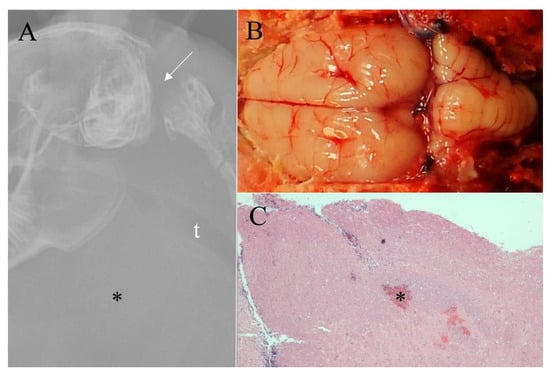

Figure 5. Eight week-old grower rabbit euthanized by mechanical cervical dislocation. (A) Survey radiograph shows a clean dislocation between the base of the skull and the first vertebrae (arrow) and marked cervical hemorrhage (*), t = trachea; (B) Grossly, no subdural dorsal hemorrhage was noted (gross score of 0/4); (C) Photomicrograph of midbrain demonstrating a lack of subdural hemorrhage (histologic score of 0/4) and minimal parenchymal hemorrhage (*) (histologic score of 1/4) (H & E, ×20).

Survey radiographs of the four growers euthanized by the NPCB device demonstrated a depressed cranium, some with skull fragments embedded in the brain and all rabbits had noticeable swelling from subcutaneous hemorrhage (Figure 3). Those euthanized by BFT varied in the degree of damage to the cranium. Two rabbits demonstrated limited, focal fractures, one rabbit had depressed fragments (i.e., compression fracture), and one rabbit (Figure 4) had two significant cranium fractures. The radiographs of the four growers euthanized by MCD showed consistent trauma resulting from complete dislocation between the base of the skull and the first vertebrae with no vertebral fractures or other dislocations (Figure 5).

Macroscopic evaluations consistently demonstrated marked brain hemorrhage for rabbits euthanized with the NPCB device. Swelling of the tissue above the skull (subcutaneous hematoma) resulted in high macroscopic subcutaneous hemorrhage scores (Figure 3). Rabbits euthanized by MCD had a small dislocation gap but a large amount of cervical hemorrhage resulting from ruptured blood vessels (Figure 5). Some rabbits euthanized by MCD had minor skull fractures of the occipital bone. This is the location the device applies pressure during application while holding the rabbit’s head in place, and in such cases a clean dislocation still occurred. Macroscopic damage resulting from BFT varied and was often not obvious (Figure 4). Damage, including fractures, was commonly noted in areas other than the targeted location for BFT, such as the back, shoulder blades, and nasal cavity. There was a statistically significant increase in brain hemorrhage score for the NPCB device compared to the other two methods, χ2 (2, n = 154) = 120.82, p < 0.001 for macroscopic subcutaneous and χ2 (2, n = 154) = 82.36, p < 0.001 for subdural hemorrhages, respectively. There was a statistically significant difference between all three methods for skull fractures, χ2 (2, n = 154) = 93.10, p < 0.001, with the NPCB device scoring the highest, followed by BFT then MCD.